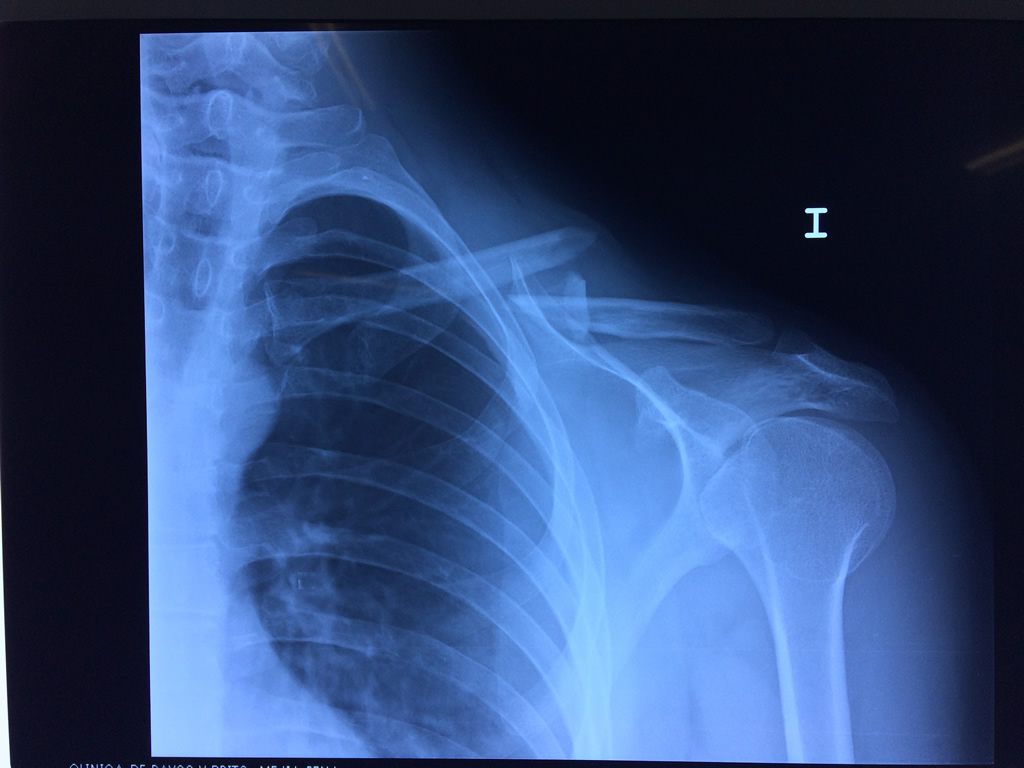

Húmero - Clavícula

La clavícula es un hueso largo, con forma de "S" itálica, situado en la parte anterosuperior del tórax. Junto con la escápula forman la cintura escapular. Se puede palpar por toda su longitud y se extiende del esternón al acromion de la escápula, siguiendo una dirección oblicua lateral y posterior.